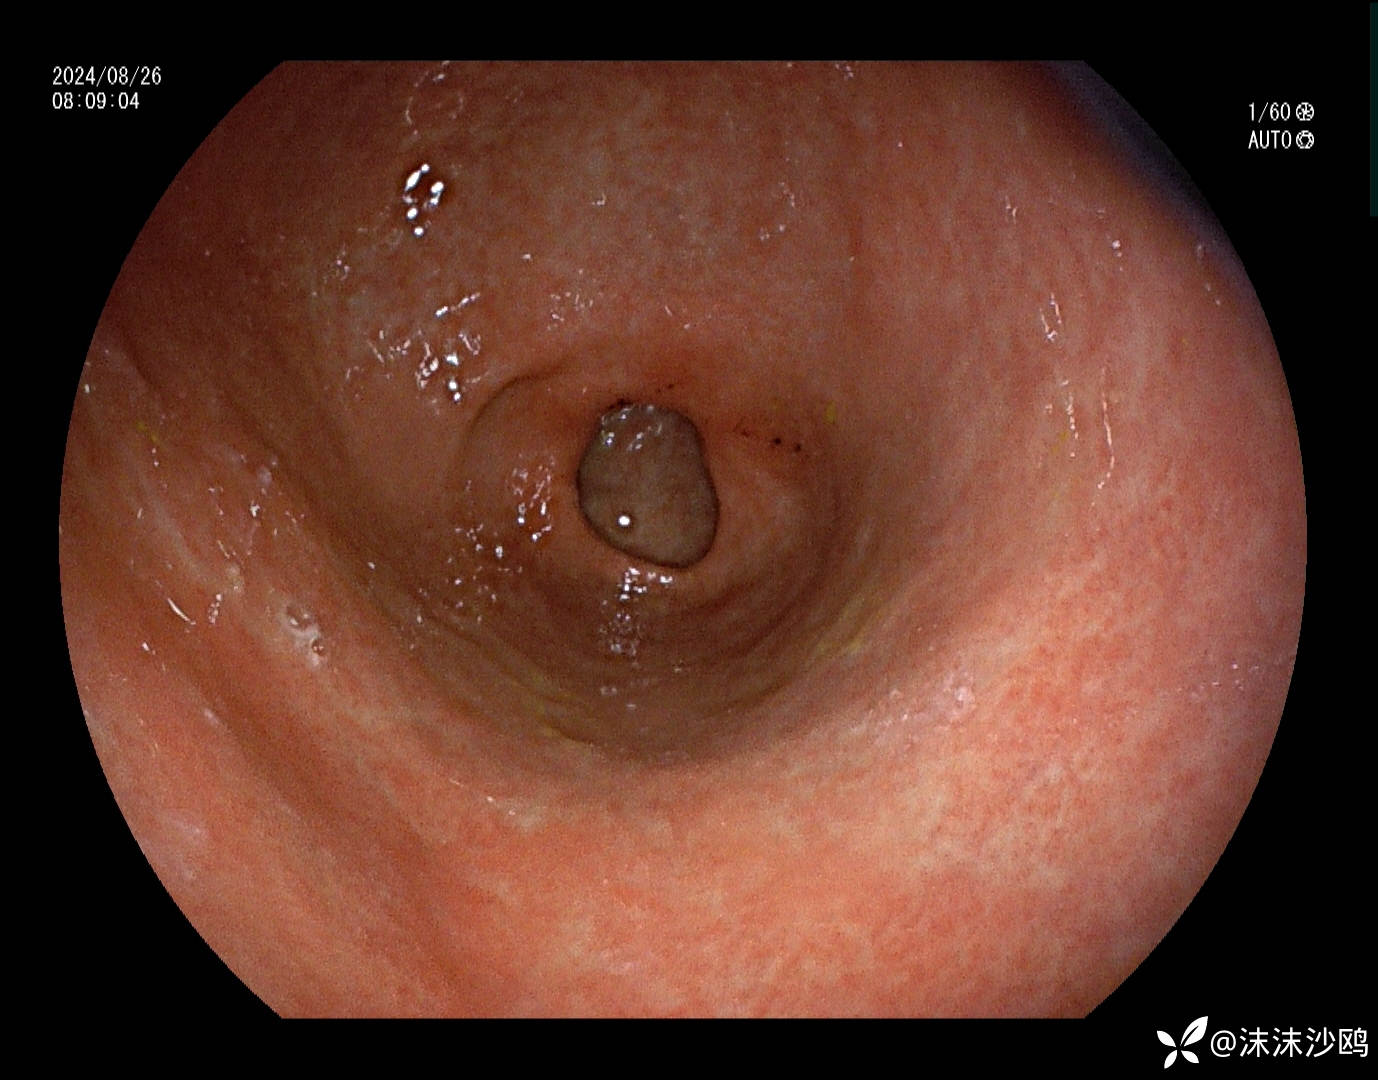

患者男性54岁,因焦虑抑郁在神经内科住院,纳差乏力行普通胃镜检查

中段食管粘膜病变,白色斑块冲洗不掉,且斑块下有粘膜下出血,是药物导致还是感染相关性的食管炎?